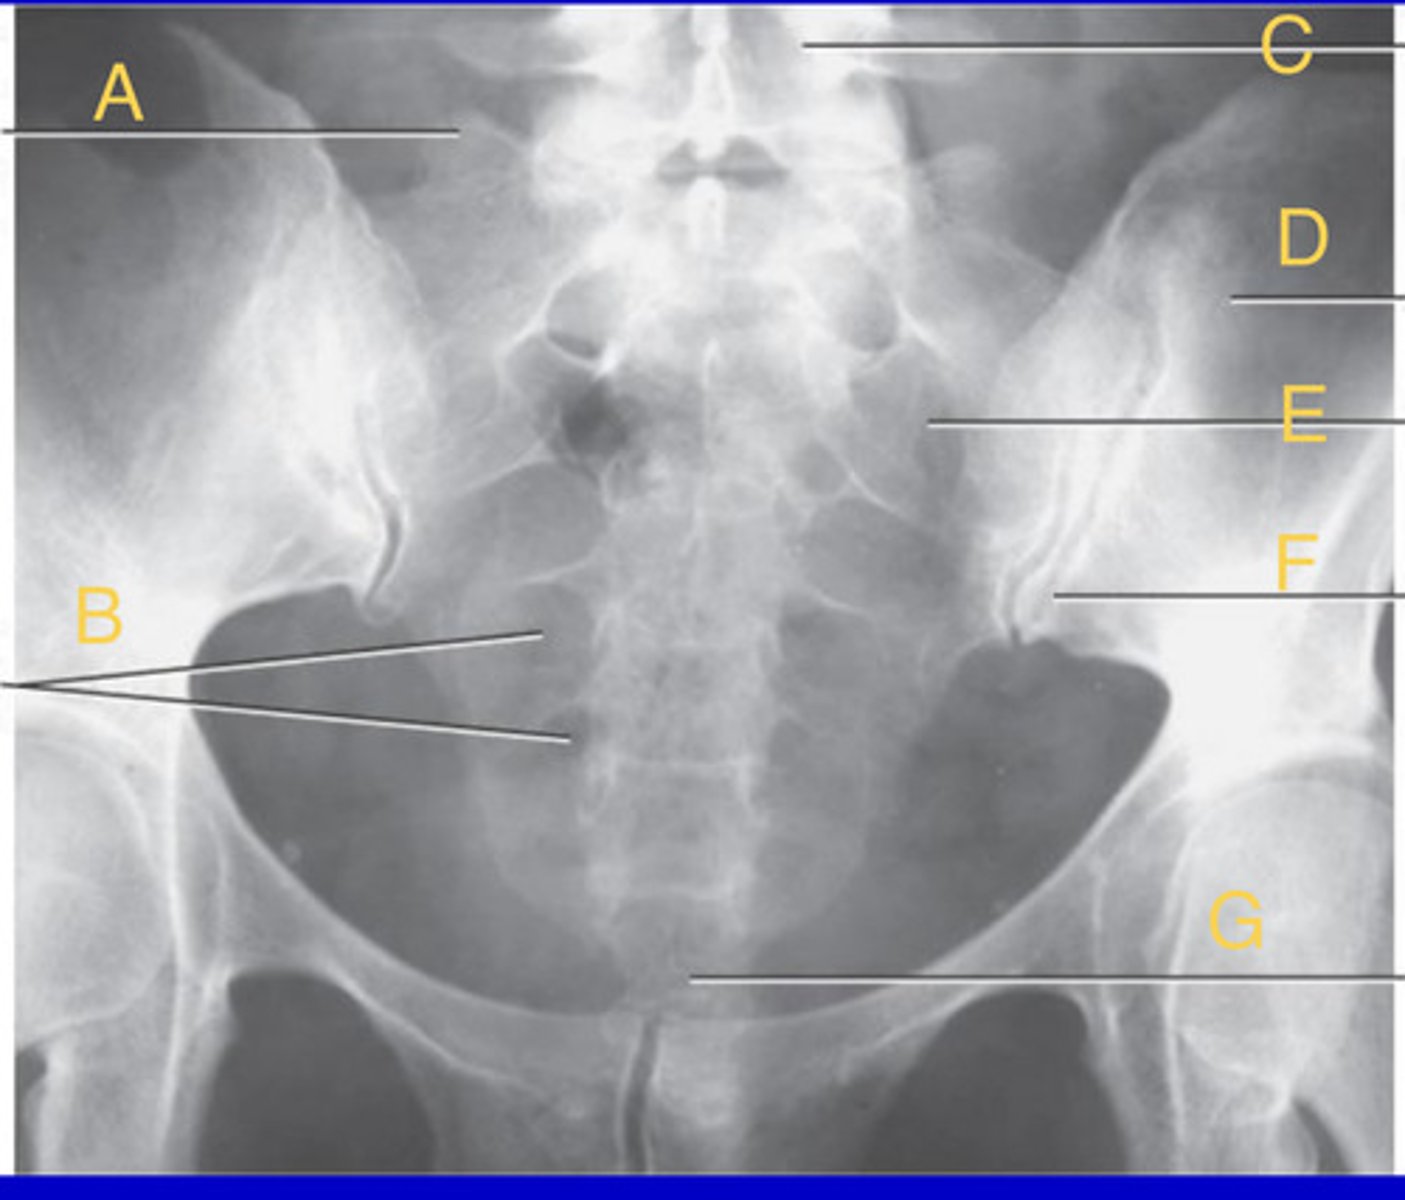

Superior articular process of sacrum

A.

Sacral foramina

B.

L5 body

C.

L ilium

D.

Sacrum

E.

Left sacroiliac joint

F.

apex of sacrum

G.

AP Axial Sacrum

What position?